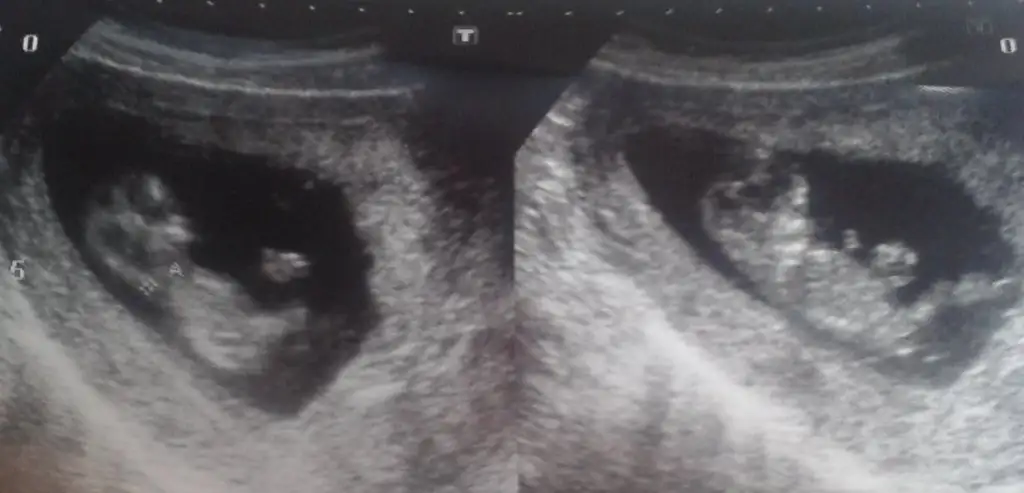

Kızlar biz de c.tesi gittik doktora 13+3 üm şu an. Doktora o kadar ısrar ettim ki cinsiyet konusunda uzun süre inceledi :)

Ama çok saklandı bizim minik Doktor da erkek olsa bi şekilde belli ederdi dedi. Göremediği için de kız olma ihtimali yüksek dediii :KK70: :KK70: Tabii gönlünden hep kız geçen ben ve eşimde çoook mutlu olduk :) Ama göremediği için hep bir pay brakıyorum kendıme sürpriz olmasın diye. Erkekte olsa yine sevinicem kimse yanlış anlamasın sağlıklı doğsun da yavruşlar.. Ama Allah biliyo içimdekini :)

Bu da son fotomuz çok küçük ama tahmini kuvvetli olan varsa onlar da yapsın bakalım :) Bir de artık şekillenmeye hareketlenmeye başladıkça, ben bi bebek taşıdığımı yeni farkedıyorum sanki :)